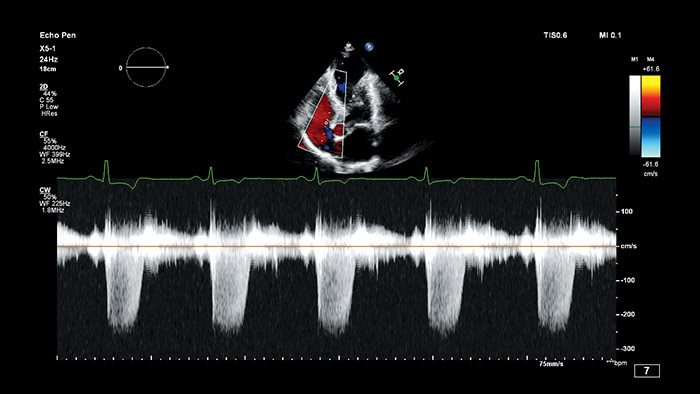

フィリップスのAnatomical Intelligence for Ultrasound(AIUS)は、高度な心臓のモデル化と実績のある定量化機能により、使いやすさ、高い再現性を実現。新しいレベルでの臨床情報の提供を可能にし、現代の医療現場が直面する経済的および臨床的課題に対応します。

AIUSは決まった手順を自動化し、ユーザーによる操作を最小限に抑えてコンピュータ主導解析を行う機能を備えています。臓器の構造を自動で認識し、解析を行うことでスクリーニング診断や計測の質を向上させ、心エコー検査をより迅速に、再現性高く実行することをサポートします。